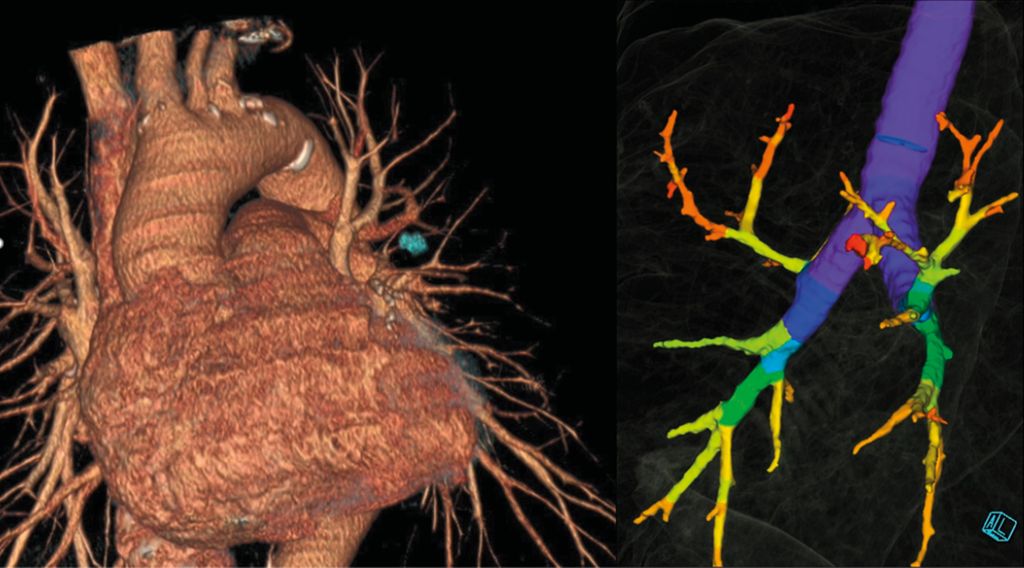

Beginnend mit der Bildgebung sollte zum initialen Staging eine Körperstamm-Computertomografie (CT) in Verbindung mit einer FGD-Positronenemissionstomografie (FGD-PET) durchgeführt werden (LoE I, A; European Society for Medical Oncology/ESMO).1 Dies ermöglicht ein entsprechendes Staging zur Planung weiterer Modalitäten. Die CT sollte, wenn möglich, nicht älter als vier Wochen sein (LoE III, B; ESMO)1, um etwaige intraoperative „Überraschungen“ zu vermeiden. Hierbei sollte auch immer an die Möglichkeit einer Segmentektomie und die damit verbundene OP-Planung gedacht werden. Da von chirurgischer Seite präoperativ die Gefäßanatomie und der Resektionsabstand eingeschätzt werden müssen, erleichtert eine Dünnschicht- bzw. High-Resolution-CT die Planung signifikant. Dies ermöglicht ebenso eine 3D-Rekonstruktion der CT, um die Segmentarterien und -bronchien darzustellen (Abb. 1).2,3

Abb. 1: Präoperative 3D-Rekonstruktion zur Segmentektomie-Planung